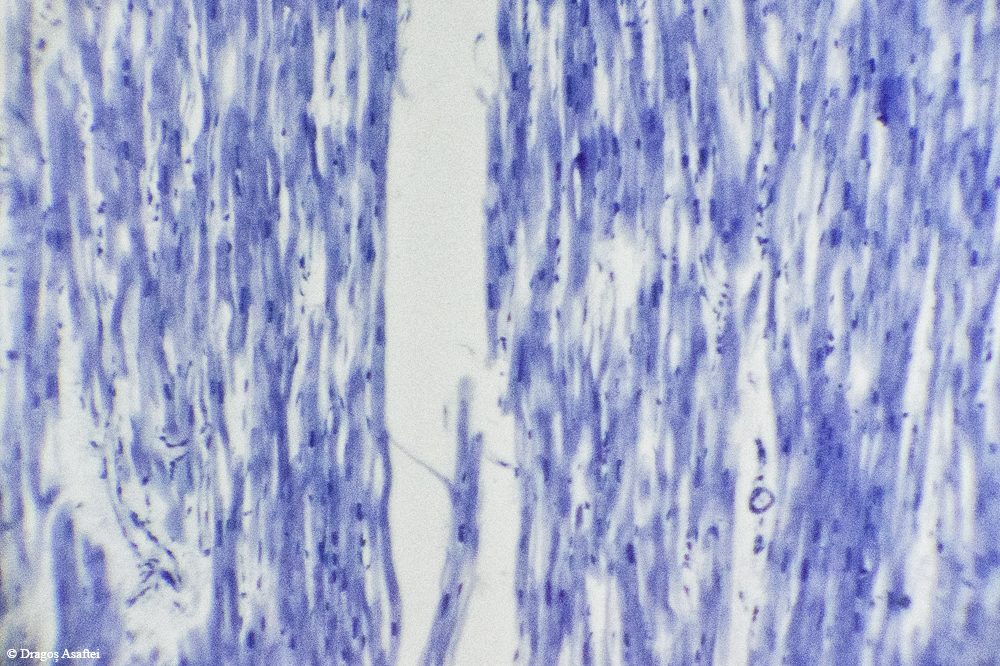

Nu știam de această metodă sau de o altă metodă viabilă pentru fotografierea prin microscop, a fost un lucru de moment care a prins foarte bine. Aveți mai jos fotografii cu următoarele țesuturi (în ordine): vena, os, cerebral, adipos, splina, mușchiul inimii, mușchi striat, mușchi, inimă.